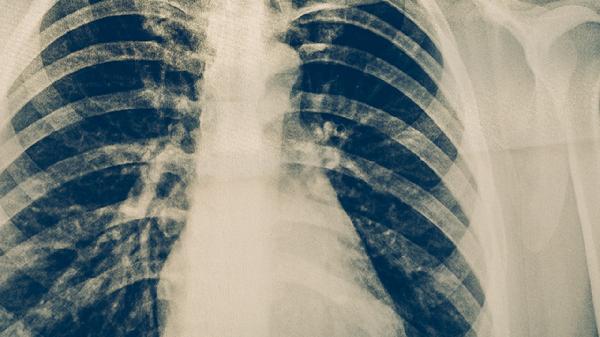

治療期間每月需復(fù)查痰涂片和胸部X線,評估治療效果。肝功能、腎功能和聽力檢查可監(jiān)測藥物副作用。完成療程后仍需每3-6個(gè)月隨訪1次,持續(xù)2年。出現(xiàn)復(fù)發(fā)癥狀如持續(xù)低熱、咳嗽加重需立即就診。